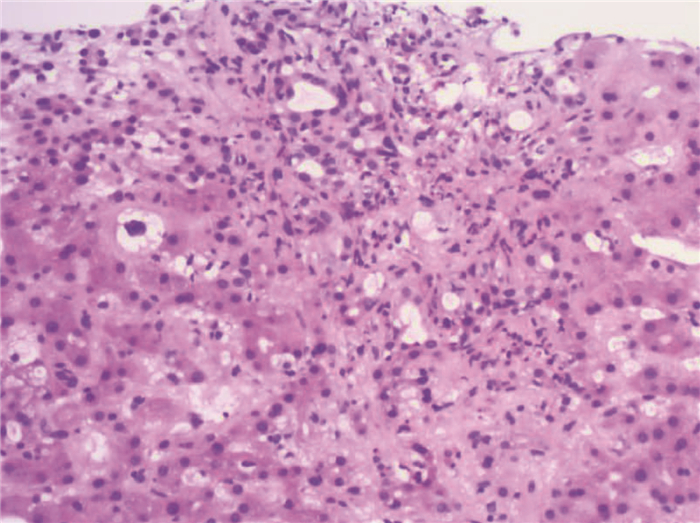

Clinical and genetic features of patients with glycogen storage disease type Ⅸa: An analysis of 20 cases

Yuchuan LI, Yi LU, Jiayan FENG, Jianshe WANG

2021, 37(2): 380-384. DOI: 10.3969/j.issn.1001-5256.2021.02.026

Abstract(1566) HTML (342) PDF (2251KB)(107)

Abstract:

Objective  To investigate the clinical and genetic features of patients with glycogen storage disease type Ⅸa (GSD Ⅸa), and to improve the clinical understanding of the disease.  Methods  A retrospective analysis was performed for the clinical data of 20 patients who were hospitalized and genetically diagnosed with GSD Ⅸa in Children's Hospital of Fudan University from January 2015 to December 2018, and their clinical and genetic features were summarized.  Results  All 20 patients with GSD Ⅸa were male, with a median age of 2.5 years at the time of confirmed diagnosis. All patients had hepatomegaly and elevated aminotransferases; of all patients, there were 5 patients (25.0%) with growth retardation, 19 (95.0%) with fasting hypoglycemia, 14 (70.0%) with hyperlactatemia, 9 (45.0%) with hypertriglyceridemia, and 5 (25.0%) with hypercholesterolemia. Fasting blood ketone was measured for 8 patients and all of these patients had an increase in blood ketone; all patients had normal uric acid, and 5 patients (25.0%) had positive urine ketone. Liver biopsy was performed for 18 patients, among whom 15 had mild to moderate liver fibrosis. A total of 16 mutations were detected in the PHKA2 gene, among which 5 were known pathogenic mutations and 11 were novel mutations, and most of the mutations were detected in the c.3614 locus. All patients were treated with uncooked cornstarch, and most patients achieved an improvement in clinical manifestations.  Conclusion  GSD Ⅸa is more common in male patients. This disease should be considered for patients with hepatomegaly, elevated aminotransferases, growth retardation, fasting hypoglycemia, elevated fasting blood ketone, and normal uric acid. Liver biopsy may help with the diagnosis of this disease, and clinical biochemical parameters and gene detection can be used to confirm diagnosis and classification. Most patients have mild clinical manifestations, while some patients may have liver fibrosis, and treatment with uncooked cornstarch can improve the condition of this disease.